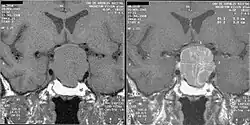

Magnetic resonance image of a pituitary macroadenoma that caused acromegaly with compression of the optic chiasm

An MRI of the brain focusing on the sella turcica after gadolinium administration allows for clear delineation of the pituitary and the hypothalamus and the location of the tumor.